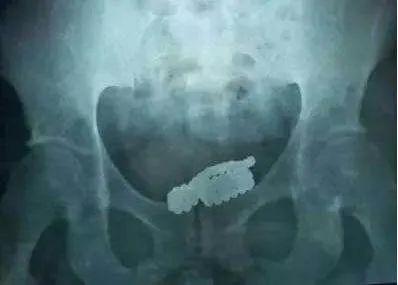

术中切开脓肿充分引流

在探查阴囊过程中

柯医生在

尿道下方触摸到一个

“马克笔”大小硬物

继续探查又发现了

3根形状各异的管状物

柯医生小心翼翼

一一将异物取出

“马克笔”硬物

足足有10厘米长,2厘米粗

是黄色管状物上面覆有结石形成的

另外三根则是形状各异的管状物